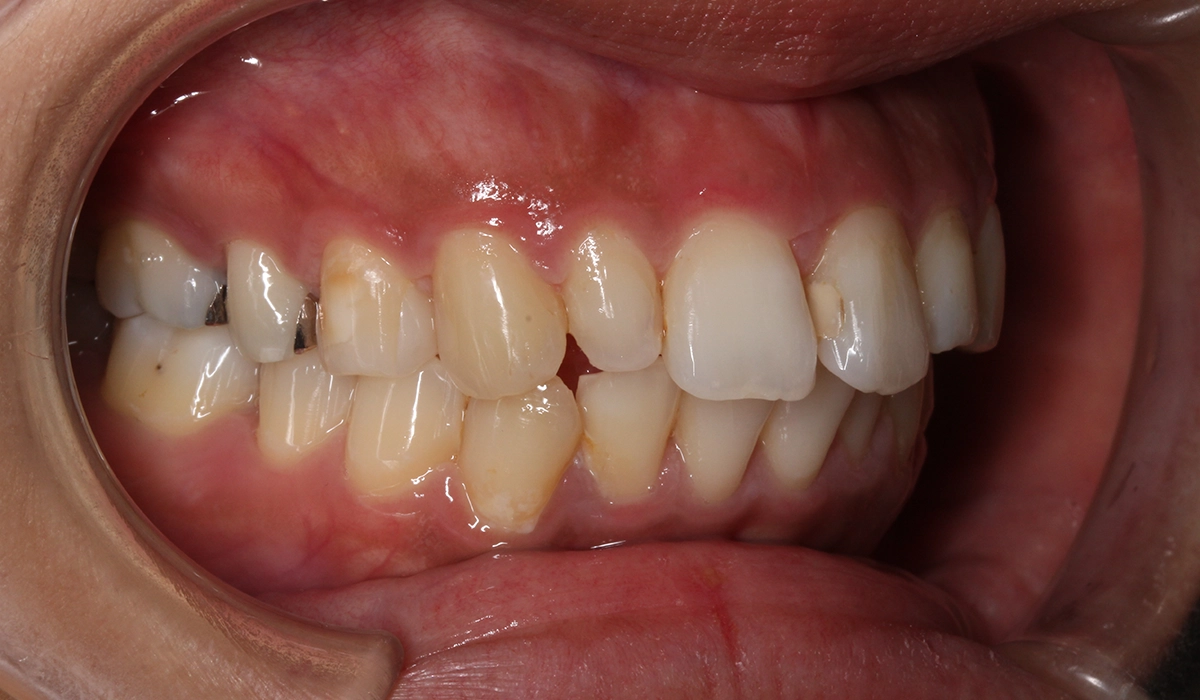

今回ご紹介する患者様は、上下の歯並びのガタツキを気にされており、矯正検査後叢生Ⅱ級と診断いたしました。

術前:左側

術後:左側